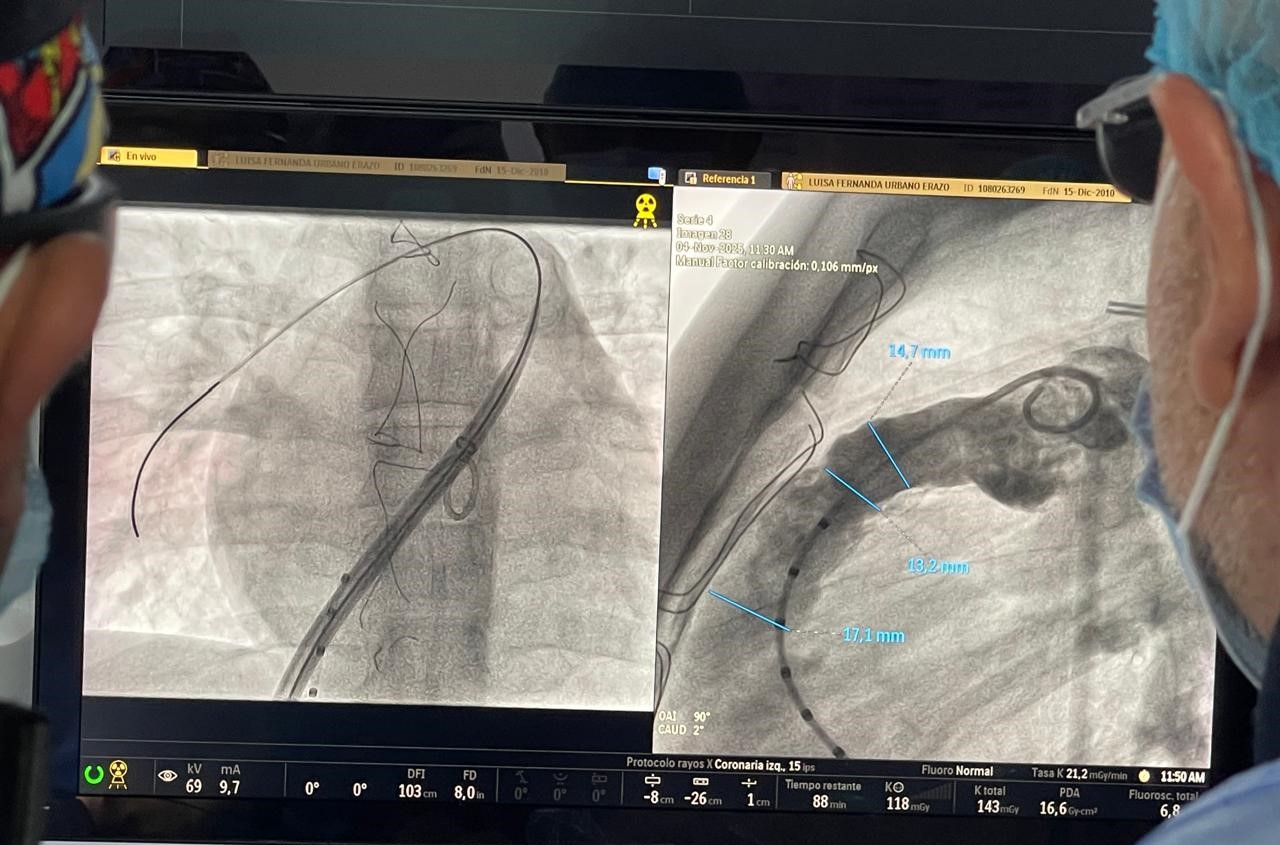

El procedimiento fue liderado por el Dr. Bernabé Martínez Amado, cardiólogo hemodinamista pediatra, junto a una cirujana cardiovascular pediátrica y cardiólogo intervencionista. El procedimiento se realizó en la sala de Hemodinamia de la sede Centro de Neiva, utilizando tecnología de última generación y rigurosos estándares internacionales de seguridad.

En lugar de abrir el tórax y exponer nuevamente el corazón, se ingresó al sistema circulatorio a través de pequeñas punciones en la pierna para llegar directamente al sitio donde la válvula debía ser implantada. En menos de tres horas, la nueva válvula pulmonar comenzó a funcionar.